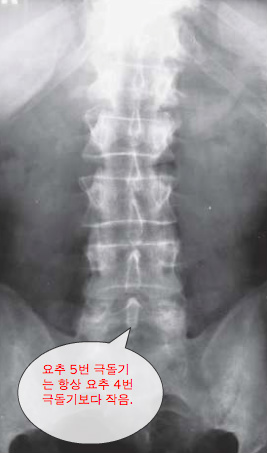

The L5 spinous process is always smaller than the L4 spinous process.

요추 5번 극돌기는 항상 요추 4번 극돌기보다 작음.

- 요추 5번 극돌기는 항상 요추 4번 극돌기보다 작음.